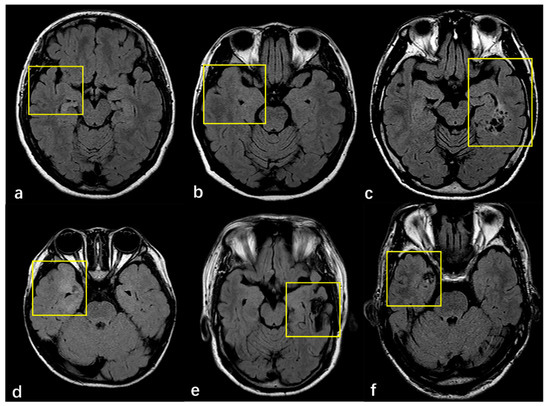

3.2. Radiologic and Pathology Findings

| MRI features of FCD | 0.680 | |||

| Cortex atrophy/thickening | 90 (13.5%) | 59 (13.4%) | 31 (13.8%) | |

| Indistinctness of the gray–white matter junction | 176 (66.2%) | 118(65.9%) | 58 (66.7%) | 1.000 |

| Intensity | 166 (62.4%) | 116 (64.8%) | 50 (57.5%) | 0.281 |

| MRI Negative | 36 (13.5%) | 19 (10.6%) | 17 (19.5%) | 0.056 |